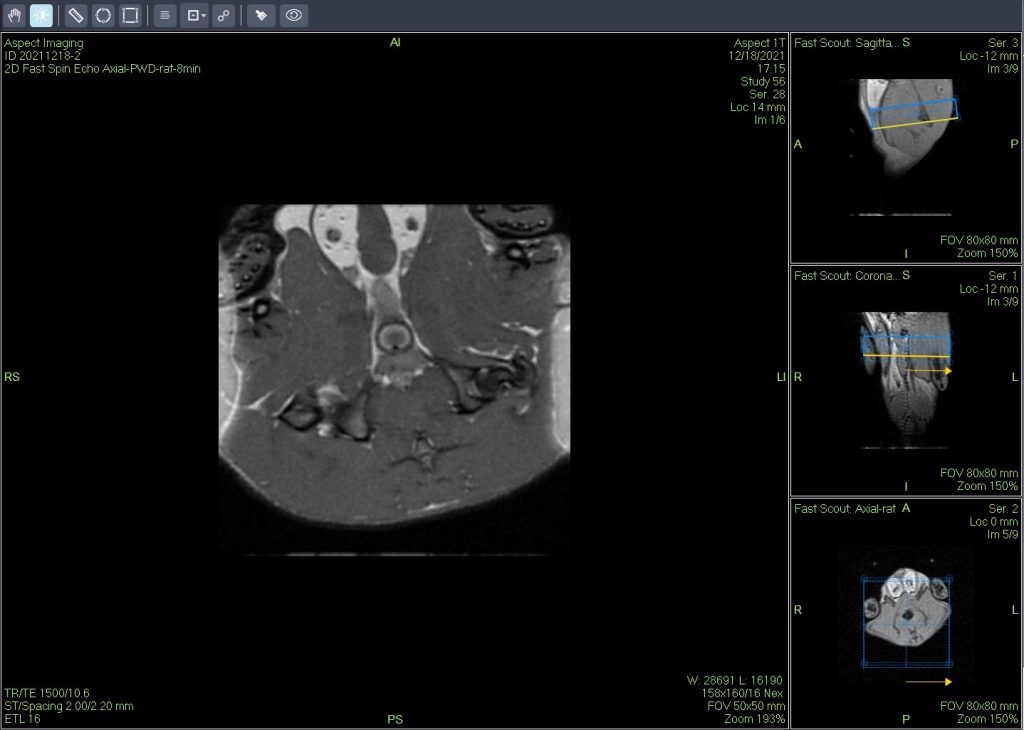

低场核磁共振技术,已被广泛应用于小动物(大、小鼠)实验模型中,用于监测体内脂肪分布及沉积情况。这不仅有助于揭示人类肥胖代谢性疾病的病因,还为肥胖治疗药物的评价提供了重要依据。通过低场核磁共振技术结果表征,科研工作者能够直观地观察到小鼠体内脂肪的变化,从而更深入地理解肥胖症的发病机制。

磁共振成像(MRI)广泛应用于临床前研究和药物开发,是一种强有力的无创性方法,可用于评估小鼠疾病模型的表型和治疗效果。

小动物磁共振成像(MRI)是一种强大的非侵入性工具,可用于检测临多种病变。

一个新的紧凑型高性能小动物磁共振成像平台(M3),该系统使用一种新的磁铁设计和一套相关的软件,降低了小动物磁共振成像仪的成本和复杂性。

Dixon脂肪抑制技术是由Dixon 提出,其基本原理是利用水、脂肪的化学位移差异,使用不同的回波时问,分别采集水和脂肪质子的in Phase 和 opposed -phase两种回波信号。